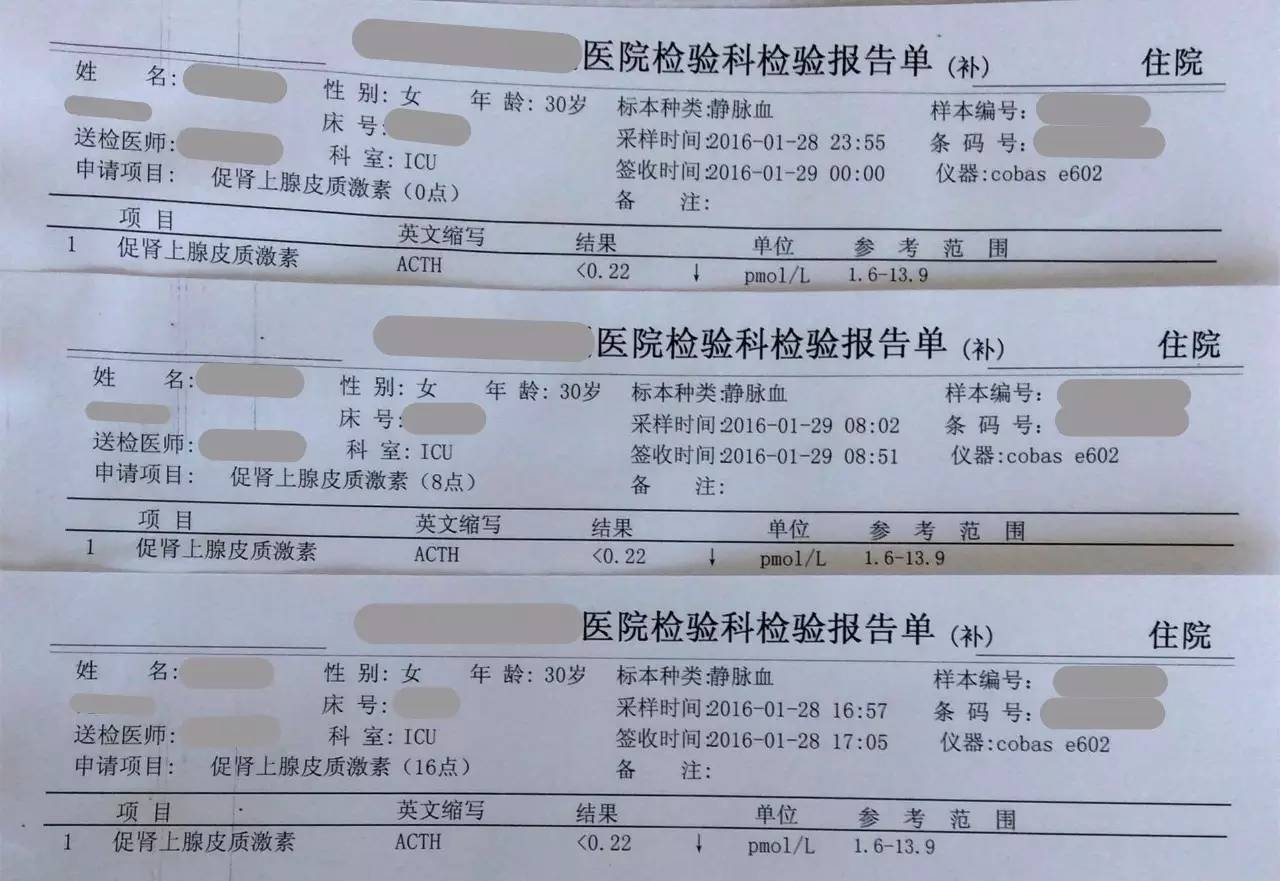

▼患者检查报告资料

目前患者面临的问题是出现了甲状腺功能减退症和肾上腺激素需要减量的问题。结合患者产后一系列的意外和抢救过程,要警惕患者出现Sheehan syndrome(希恩综合征),因为低血压、出血等等引起垂体缺血缺氧所致。

2.患者应用甲强龙,当时是因为出现了休克为了抢救所用,目前情况明细好转,可以每周(也就是贵院内分泌大夫会诊的7~10天)减量甲强龙1片(4mg); 但因为患者可能存在继发性肾上腺皮质功能减退症(继发于希恩综合征),减量到全天2片时需要评估清晨未服药前ACTH和血皮质醇、电解质、性腺激素六项来评估是否能够完全停药,还是需要减成替代剂量,此时可以应用泼尼松来替代甲强龙,泼尼松一片是5mg,等效于甲强龙1片,4mg,如果确实出现肾上腺皮质功能减退,可以逐渐减量到泼尼松全天1片(2.5mg,早上和下午各服用一片)。到时候再根据患者复查的情况判断肾上腺功能的恢复情况。